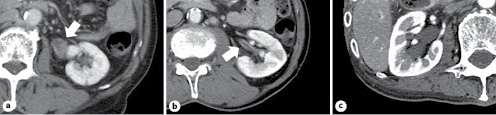

Table 1 shows the findings of the examination and management of 31 patients with atypical urinary cytology of the upper urinary tract. According to the initial CT findings in the upper urinary tract, we divided the patients into 4 groups: tumor-like lesions in 11 (Group A; Fig. 1a), wall thickening without tumor-like lesions in 8 (Group B; Fig. 1b), hydronephrosis without tumor-like lesions or wall thickening in 4 (Group C; Fig. 1c), and normal findings in 8 (Group D).

In Group A, all 11 patients underwent nephroureterectomy and UTUC was confirmed histologically. Five patients had undergone nephroureterectomy immediately, without repeated RP, ureterorenoscopy, or biopsy. In Group B, UTUC was revealed in 3 of 8 patients and the remaining 5 patients were under surveillance without evidence of UTUC at the median follow-up period of 47 months (23–132 months). In Group C, UTUC developed in one of 4 patients; this patient was diagnosed with UTUC by nonscheduled RP following positive voided urinary cytology and appearance of tumor-like lesions in the ureter upon CT analysis. In Group D, UTUC was revealed in 2 of 8 patients. One positive patient had an extremely small tumor at the vesicoureteral junction that was revealed by ureterorenoscopy; this tumor was resected endoscopically. The other was diagnosed with carcinoma in situ of the upper urinary tract by repeated RP.